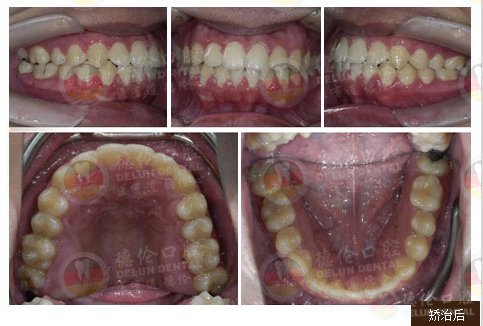

女 13岁

牙齿症状:上下前牙前突、唇倾,上下牙弓散在间隙

矫治方法:SPEED矫治器结合种植钉、整体内收上下牙弓、改善双牙弓前突以及凸面型侧貌